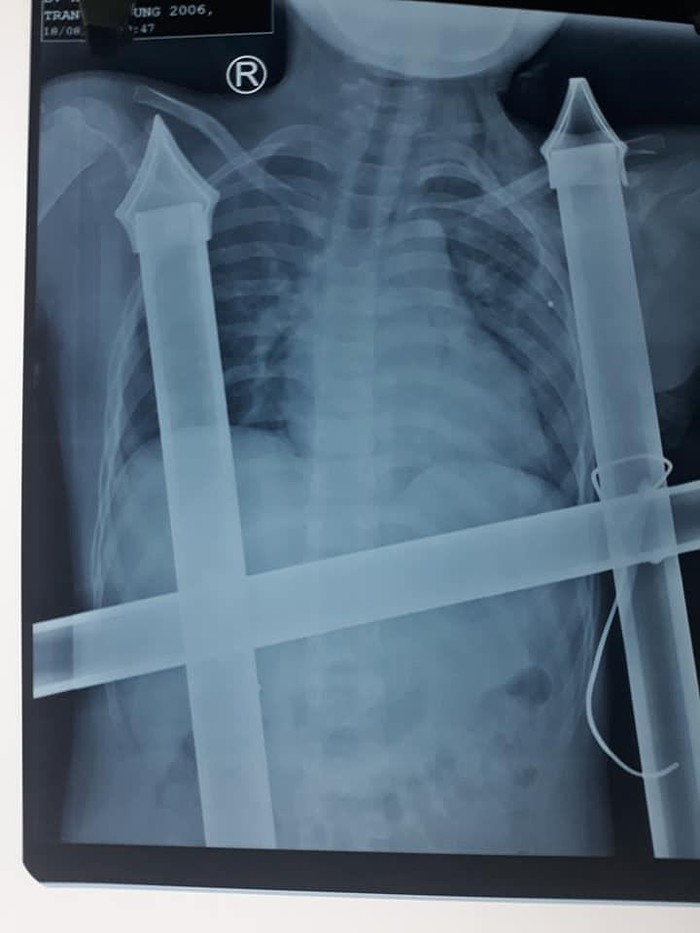

![]() |

| Phim chụp X - quang của cháu Trần Anh D. |

Bác sĩ Chuyên khoa I Hồ Thái Phúc, Khoa Phẫu thuật tim mạch lồng ngực (Bệnh viện Hữu nghị Đa khoa Nghệ An) cho biết: “Qua hình ảnh phim X - quang, các bác sĩ xác định vết đâm của ngạnh sắc nhọn hàng rào đã chạm tới nền đầu của bệnh nhân.

Êkip phẫu thuật đã cố gắng tháo đầu sắc nhọn này, và sẵn sàng xử lý các tình huống tổn thương các mạch máu lớn, gây nên tình trạng chảy máu ồ ạt, đe dọa tính mạng của bệnh nhi ngay trên bàn mổ”.

Theo bác sĩ Phúc, may mắn là vật sắc nhọn không làm mạch máu lớn và nội tạng bị tổn thương. Bệnh nhân bị đứt cơ ngực lớn, cọc sắt hàng rào tạo nên đường hầm trong khoang ngực kéo dài trên 10cm. Chúng tôi đã rút được dị vật ra khỏi cơ thể cậu bé an toàn. Đồng thời, lau rửa, sát trùng vết thương, dẫn lưu đường hầm, khâu cơ ngực lớn và da liền lại.